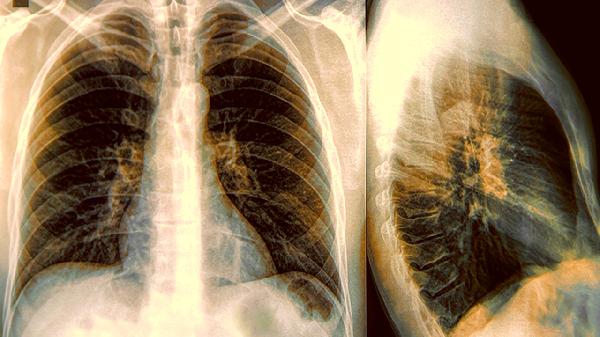

肺變白通常指影像學(xué)檢查中肺部出現(xiàn)大面積白色陰影,可能與肺炎、肺水腫、肺纖維化、肺結(jié)核、肺癌等疾病有關(guān)。肺變白屬于影像學(xué)描述,需結(jié)合臨床表現(xiàn)和其他檢查明確具體病因。

肺炎是肺部感染引起的炎癥反應(yīng),影像學(xué)可表現(xiàn)為肺變白。肺炎可能與細菌、病毒、支原體等病原體感染有關(guān),通常表現(xiàn)為咳嗽、咳痰、發(fā)熱、胸痛等癥狀。治療肺炎可遵醫(yī)囑使用阿莫西林膠囊、鹽酸左氧氟沙星片、阿奇霉素分散片等藥物。建議患者多休息,適量飲水,保持室內(nèi)空氣流通。

肺水腫是肺部血管內(nèi)液體滲入肺泡和肺間質(zhì)導(dǎo)致的病變,影像學(xué)可表現(xiàn)為肺變白。肺水腫可能與心力衰竭、腎功能不全、吸入有毒氣體等因素有關(guān),通常表現(xiàn)為呼吸困難、端坐呼吸、咳粉紅色泡沫痰等癥狀。治療肺水腫可遵醫(yī)囑使用呋塞米片、硝酸甘油片、鹽酸嗎啡注射液等藥物。建議患者控制液體攝入量,避免劇烈運動。

肺纖維化是肺部組織異常增生和瘢痕形成的病變,影像學(xué)可表現(xiàn)為肺變白。肺纖維化可能與長期吸入粉塵、自身免疫性疾病、藥物副作用等因素有關(guān),通常表現(xiàn)為進行性呼吸困難、干咳、乏力等癥狀。治療肺纖維化可遵醫(yī)囑使用吡非尼酮膠囊、尼達尼布軟膠囊、甲潑尼龍片等藥物。建議患者避免接觸刺激性氣體,適當(dāng)進行呼吸功能鍛煉。

肺結(jié)核是結(jié)核分枝桿菌感染引起的慢性傳染病,影像學(xué)可表現(xiàn)為肺變白。肺結(jié)核可能與免疫力低下、密切接觸結(jié)核患者等因素有關(guān),通常表現(xiàn)為長期低熱、盜汗、消瘦、咳嗽等癥狀。治療肺結(jié)核可遵醫(yī)囑使用異煙肼片、利福平膠囊、吡嗪酰胺片等藥物。建議患者保持良好作息,加強營養(yǎng)支持。

肺癌是肺部惡性腫瘤,影像學(xué)可表現(xiàn)為肺變白。肺癌可能與長期吸煙、空氣污染、職業(yè)暴露等因素有關(guān),通常表現(xiàn)為咳嗽、咯血、胸痛、消瘦等癥狀。治療肺癌可遵醫(yī)囑使用吉非替尼片、奧希替尼片、培美曲塞二鈉注射液等藥物。建議患者戒煙,避免接觸二手煙,保持樂觀心態(tài)。

肺變白是多種肺部疾病的影像學(xué)表現(xiàn),建議及時就醫(yī)完善相關(guān)檢查明確診斷。日常生活中應(yīng)注意避免吸煙和接觸有害氣體,保持室內(nèi)空氣清新,適當(dāng)進行有氧運動增強肺功能。出現(xiàn)持續(xù)咳嗽、呼吸困難等癥狀時應(yīng)盡早就診,遵醫(yī)囑進行規(guī)范治療。飲食上可適量增加富含優(yōu)質(zhì)蛋白和維生素的食物,如雞蛋、牛奶、新鮮蔬菜水果等,有助于肺部健康。